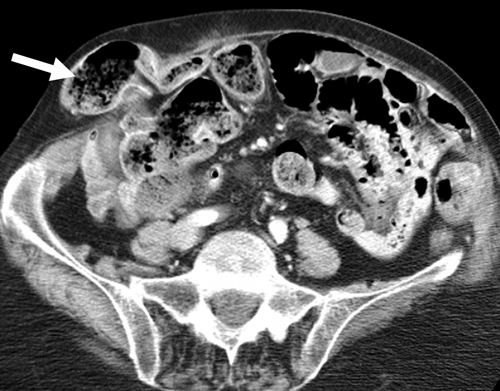

Diagnóstico de hernia inguinal. Se denomina hernia a la parte de un órgano que sobresale a través de una abertura anormal o de manera anormal. La hernia de ingle (inguinal) ocurre cuando una parte del intestino sale a través de un punto débil de la pared abdominal en...